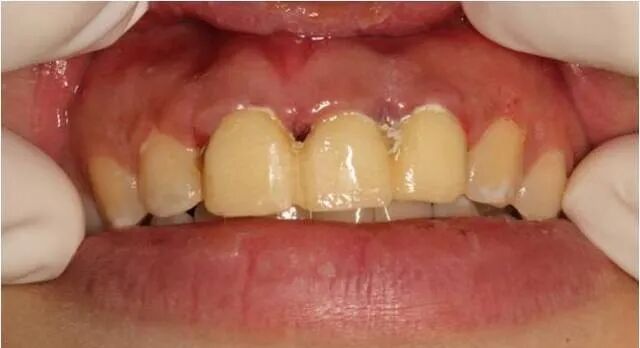

患者自述3年前上前牙因外伤折断在外院做烤瓷牙修复,现烤瓷修复体脱落。

经过检查发现,患者外露牙体组织不够,无法直接进行烤瓷牙重置。建议通过冠延长手术的方法,来使患牙的暴露量增加,然后再通过烤瓷牙进行牙齿的修复及改善牙龈形态的美观。与患者商议,表示接受该修复方案。

临时冠修复

术后两周拆线后口内情况

固定修复后口内像

修复前后对比图